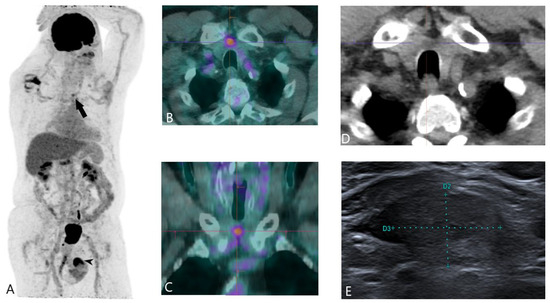

Thyroid crisis caused by metastatic thyroid cancer: an

Thyroid crisis caused by metastatic thyroid cancer: an